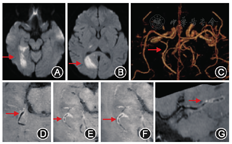

NCCT是临床确诊急性脑出血的首选方法,是脑出血检测的"金标准"。NCCT用于脑血管病的辅助检查需要注意以下几点:(1)对于急诊疑似脑卒中患者首选NCCT,可以明确患者是否有脑出血或蛛网膜下腔出血(subarachnoid hemorrhage,SAH),病灶呈现高密度影,为临床进一步诊治提供重要信息。在疾病的恢复期和慢性期,CT呈低密度影。(2)对疑似SAH患者,首选头颅CT检查。螺旋CT检测的阳性率可达98%~100%。但需要考虑就诊时间,发病24 h后,阳性率开始递减,出血5 d后,阳性率只有50%。SAH患者需要进一步行CTA/DSA以排除动脉瘤。(3)对脑出血患者,NCCT可以提示早期血肿扩大的征象(图1),目前大家比较认同的几个征象为:岛征、黑洞征、混合征、血肿内低密度、血肿边缘不规则和混合密度征,其预测血肿扩大的敏感度、特异度不完全相同[4]。岛征预测血肿扩大的敏感度、特异度分别为44.7%、98.2%[5];黑洞征预测的敏感度、特异度分别为39.3%、95.5%[6,7];混合征预测的敏感度、特异度分别为39.3%、95.5%[8]。(4)对于缺血性脑卒中患者,早期行NCCT的敏感度并不高,一般在发病24 h后,缺血性病灶才开始明显,表现为低密度改变;但早期可见大脑中动脉高密度征,预测大动脉闭塞的敏感度为67%,特异度为82%[9]。陈旧性缺血性脑卒中患者头颅NCCT低密度病灶需要与陈旧性脑出血低病灶相鉴别(图2),后者在T2WI表现为低密度病灶周边低信号环,系含铁血黄素沉积所致。

CTA是指静脉注射含碘造影剂后的CT扫描,计算机对图像进行三维重建及数字减影,可清晰显示脑动脉的血管结构,如Willis环,大脑前、中、后动脉及其主要分支,可对脑血管病变提供重要的诊断依据。

与磁共振动脉成像(magnetic resonance angiography,MRA)相比,CTA能够更好地显示脑血管三维空间的立体结构,可以进行任意方位和角度旋转,可以清晰地显示血管狭窄或动脉瘤,进行明确定位[10,11]。CTA的缺点为需要造影剂,受颅底骨质影响,如在海绵窦段的颅内动脉瘤,常常容易漏诊。但对SAH后的动脉瘤检测优于MRA。所以对于急诊疑似脑卒中的患者,为进一步明确是否有大血管狭窄或动脉瘤,均建议行CTA检查,指导取栓或动脉瘤介入/手术治疗。